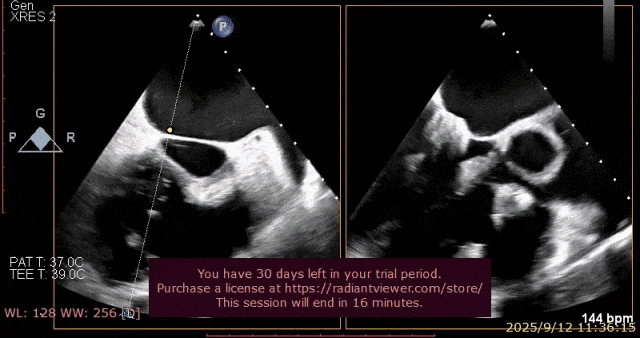

心脏超声示左室增大,二尖瓣2、3区脱垂伴重度反流(腱索断裂),Carpentier分型Ⅱ型,典型Barlow综合征表现;二尖瓣开放面积5.0cm²,3区瓣环内径31mm,前叶长22mm、后叶17mm,前叶收缩期关闭瓣体部分呈拱形突向左房腔,瓣膜游离缘对合欠佳,可见腱索断裂,长度9mm;2区瓣环内径32mm,前叶长22mm、后叶10mm,前后叶均可脱垂;三尖瓣重度反流。CDFI示瓣口重度偏心性反流,反流束沿主动脉后壁走行,肺静脉收缩期可见反向频谱。

术前超声

图片

术前瓣叶

术前反流

术前3D